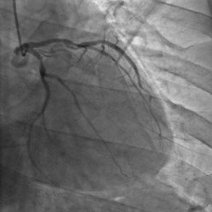

- 冠状动影怎么做一、冠状动影怎么做二、冠状动术前准备三、冠状动影注意事冠状动影怎么做1、冠状动影怎么做冠影检查是目前唯一直接察冠状动形态的方法,号称冠心病断的标准

- 冠状动脉造影手术过程,一,冠脉造影的适应症冠脉造影的主要目的是明确有无冠状动脉疾病,选择治疗方案和判断预后,有心绞痛症状的患者,尤其是药物治疗无效或者通过无创检查发现有高危因素的患者应行冠状动脉造影术,对拟形瓣膜性心脏病或先天性心脏病手术的

- 手把手教你做冠影现段,冠状动影仍然是冠心病断的手段,为实现今天做影,明天就上班的安全、准确,熟练掌握冠状动影技术是中之。作|大军孔令秋来源|孔瘦本期,我们用步步为